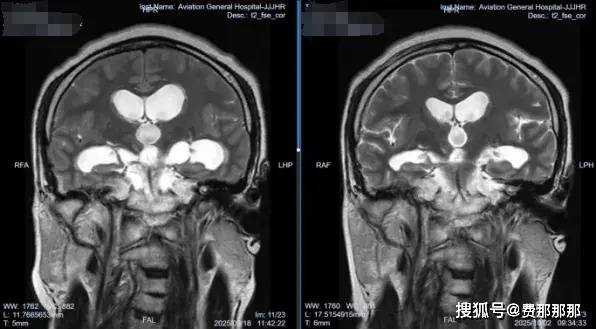

回顾文章开头提到的内蒙古患者图某的情况,他入院后,肖庆教授团队为他做了详细的检查。眼科会诊发现他已有视野缺损和视神经乳突水肿,这表明他的颅内高压已经持续了一段时间,并对视神经造成了损害。他的头颅CT/MR检查显示多发囊性占位,视交叉受压改变,结合他的流行病学史,可以明确脑囊虫病诊断。

术中内镜下可见右侧脑室壁粗糙,广泛炎性黄白色突起肉芽增生——这是既往有过颅内感染的典型表现。肖庆教授更加坚定了之前的判断,进行第三脑室底造瘘,并在基底池内取出数枚囊虫占位,大者外观达2*2cm;同时探查发现基底池内部有多发黄色网状粘连,基底动脉搏动差。